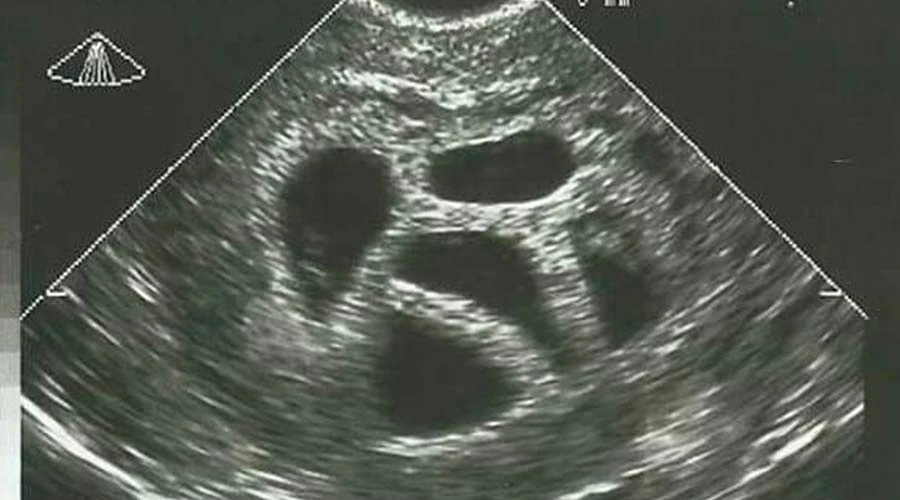

Susan compartió la imagen de la ecografía en septiembre de 2015. En ella se observan cinco sacos gestacionales, que corresponden a sus cinco hijos, hoy de 20 años.